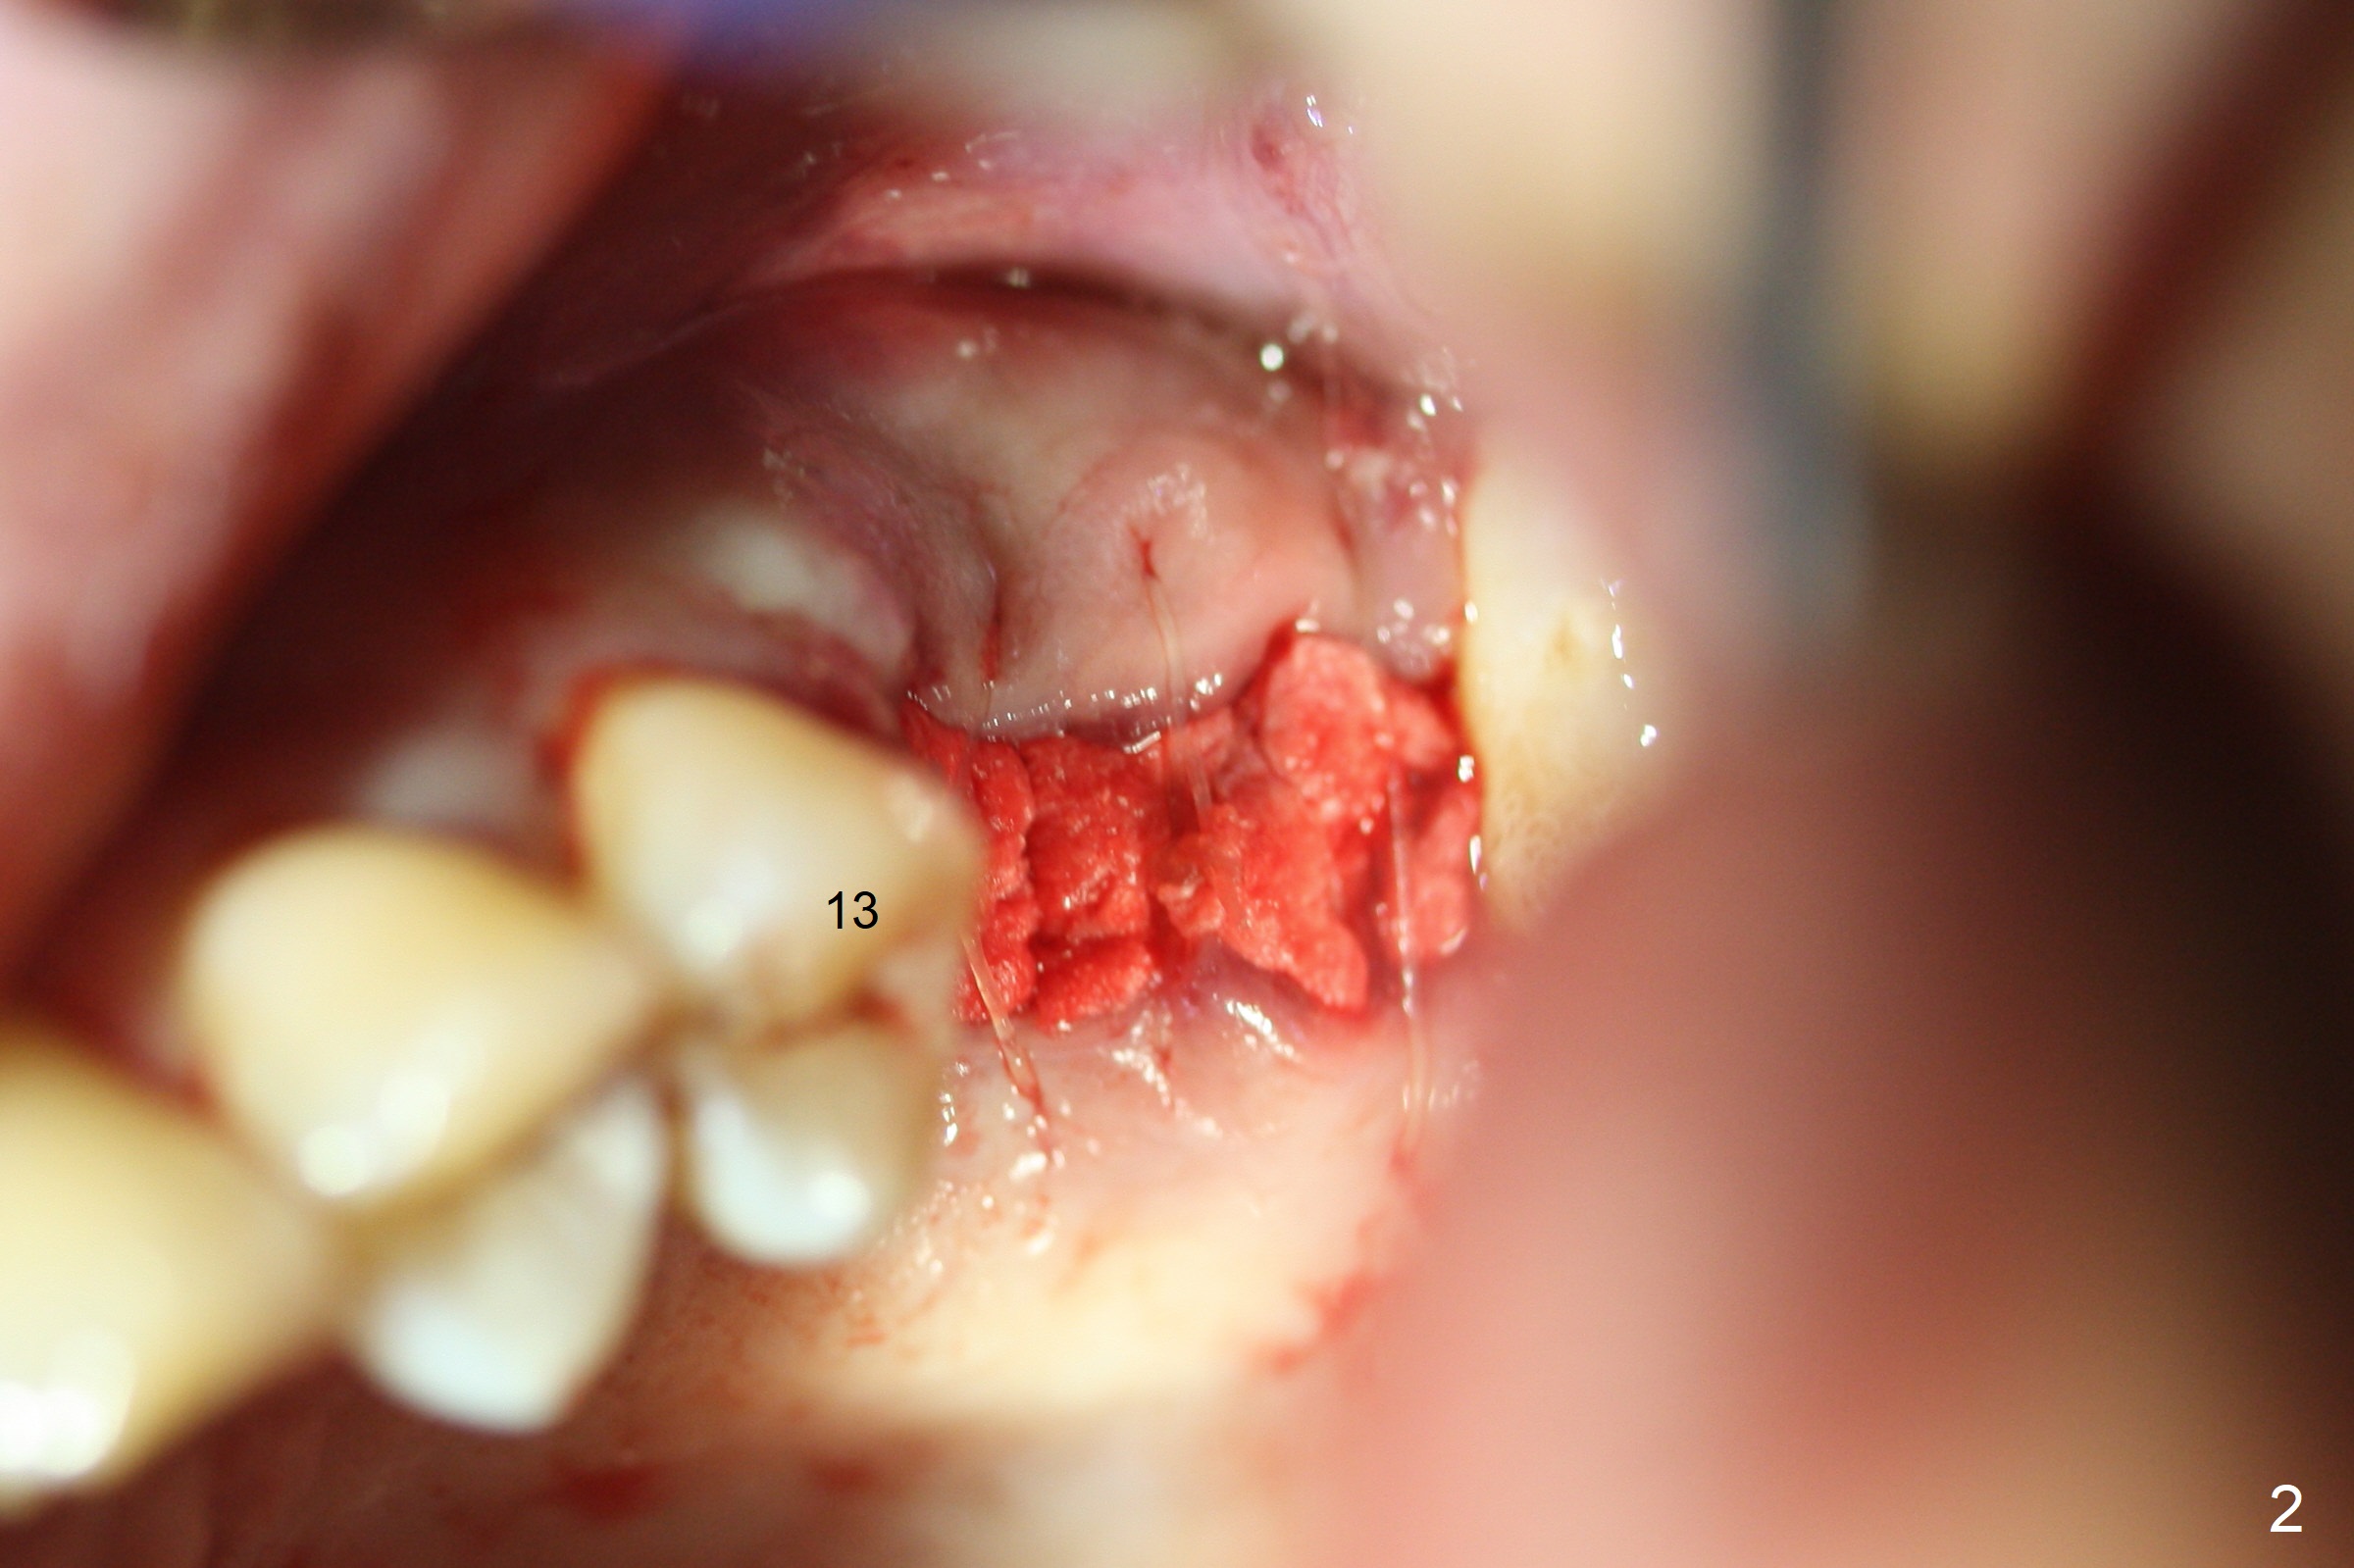

A 34-year-old man (smoker (4 cigarettes per day)) has advanced periodontitis (Fig.1). After upper quadrant SRP, the teeth #14 and 15 are extracted with removal of granulation tissue from #14 palatal socket. Following copious irrigation with NS, a 10x20 mm Osteogen plug is inserted into #14 and 15 sockets. The plug is fixed in place with 4-0 Chromic Gut suture (2 of figure-8 fashion, Fig.2).